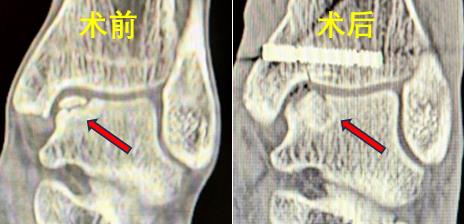

骨科副主任医师张克祥介绍,在日常生活中,“崴脚”,即踝关节扭伤,是导致距骨软骨损伤的常见原因,但由于软骨自我修复能力较差,所以软骨损伤是公认的治疗难题。针对患者病情,团队经过讨论,决定采用自体骨膜 - 骨栓移植技术修复损伤区,同时为其定制3D打印导板,以实现精准截骨,缩短手术时间、减少副损伤。

手术当日,在麻醉科团队的密切配合下,张克祥带领手术团队先通过关节镜彻底清理踝关节内增生滑膜及疤痕组织,再使用3D打印导板于内踝截骨,显露软骨损伤区并彻底清理病灶组织;随后,从患者自身髂骨提取带骨膜的骨栓,将其植入距骨软骨损伤处,整个手术过程顺利,患者术中生命体征平稳。术后,在护理团队的精细化理疗与康复指导下,患者踝关节疼痛症状显著缓解,目前已逐步进行功能锻炼,患者对治疗效果非常满意。